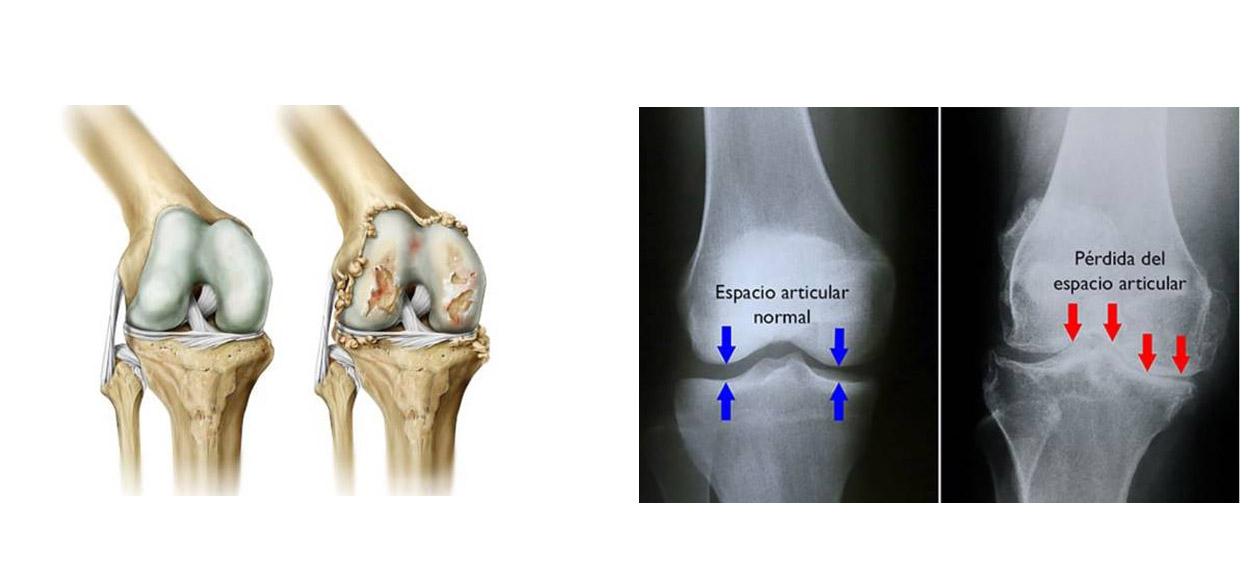

En la rodilla es por tanto una enfermedad de larga evolución, causada por los cambios degenerativos de la superficie articular de los huesos que la componen, el fémur, la tibia y la rótula. Cuánto está muy avanzada, afectan también estructuras internas de la rodilla como meniscos y ligamentos, hasta llegar al roce de un hueso contra otro. Estos cambios habitualmente se acompañan de una deformidad progresiva de la rodilla, hacia adentro o afuera según sea el caso y una pérdida progresiva de la movilidad.

En la mayoría de los casos será necesaria la realización de un estudio radiológico completo, que debería incluir las dos rodillas en proyección anteroposterior y lateral, idealmente con el paciente en posición de pie, para poder valorar el estado real de la articulación y el efecto de la carga del peso corporal sobre la misma.

Está mostrará en cada caso el grado de pérdida del cartílago articular, el pinzamiento y estrechamiento de la zona más afectada de la rodilla, así como la deformidad y formación anormal de hueso periférico. En el estado más avanzado es evidente el contacto hueso - hueso y la pérdida de la congruencia articular.